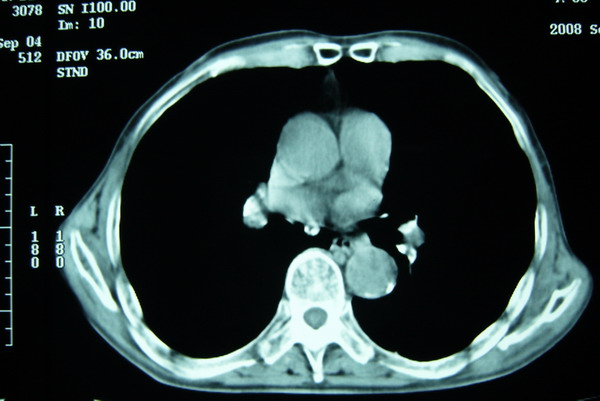

标题: CT15579:男 86岁 咳嗽 咳少量白痰 发热2天 吸烟史60年 [打印本页]

标题: CT15579:男 86岁 咳嗽 咳少量白痰 发热2天 吸烟史60年

右肺上叶巨大软组织肿块,轮廓不规则,纵隔内有肿大淋巴结,首先考虑肺癌。

右上肺一不规则团块,边缘有分叶和毛刺,纵隔有淋巴结肿大。右肺周围性肺癌首先考虑。